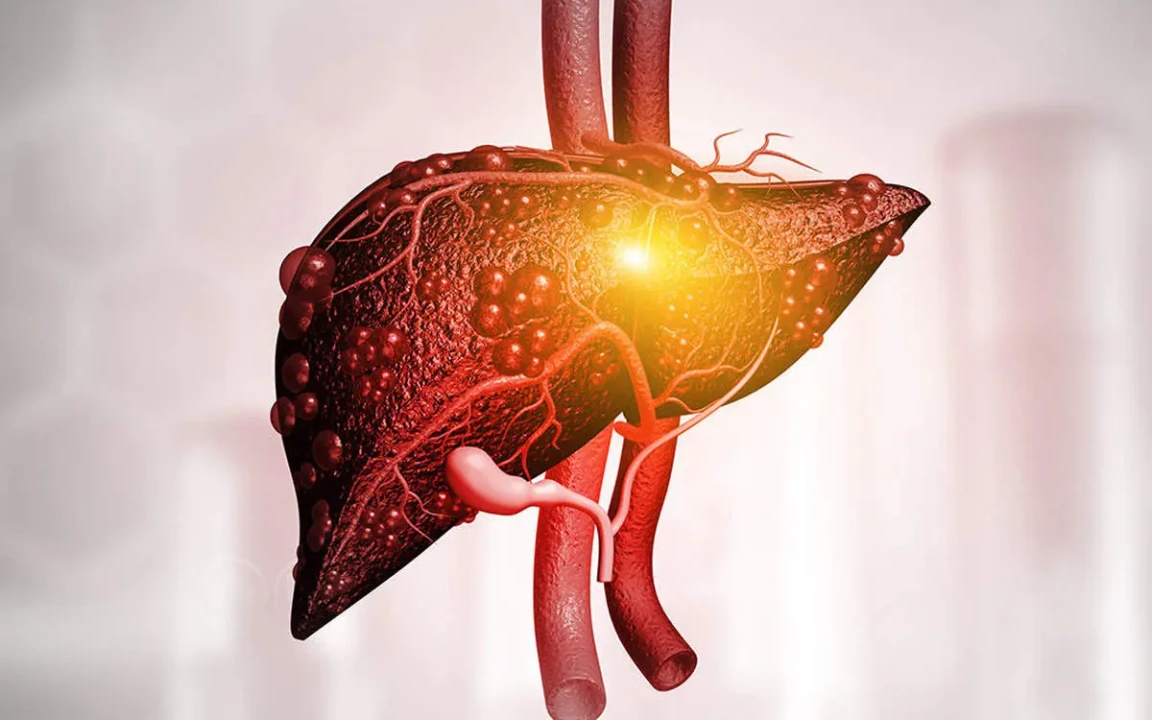

به گزارش پارسینه و به نقل از چربی در قسمت های مختلفی از بدن برای تولید انرژی و عایق شدن بدن دربرابر سرما ذخیره می شود. چنانچه این چربی در کبد ذخیره و زیاد شود ممکن است منشا بیماری کبد چرب باشد که تغییرات در رژیم اولین روش درمانی این بیماری خواهد بود. افراد مبتلا به کبد چرب با رژیم غذایی مناسب و کاهش وزن صحیح بهبود پیدا می کنند.

دونوع بیماری کبد چرب وجود دارد: بیماری کبد چرب الکلی و غیر الکلی.

بارداری نیز می تواند علت بیماری کبد چرب باشد. بیماری کبد چرب به کبد آسیب رسانده و از دفع سموم و تولید بیلی رویین در دستگاه گوارش جلوگیری می کند. هنگامی که در عملکرد کبد اختلال ایجاد شود فرد در معرض مشکلات دیگری نیز قرار می گیرد. تغییرات رژیم غذایی و ورزش منظم روش های اصلی در مدیریت این بیماری هستند اما با این حال ممکن است برخی از افراد برای معالجه به پزشک نیز مراجعه کنند.